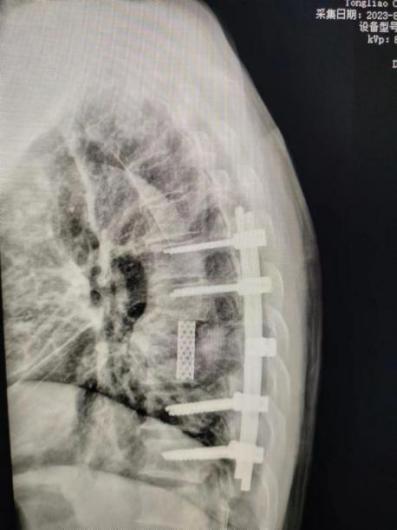

科室团队在经过精细讨论,通过MDT多学科会诊后,充分评估了该患手术风险及预后,术前给予抗结核药物治疗,同时为其在全麻下行胸椎后路经椎弓根环形减压病灶清除椎间融合内固定手术。术后患者双下肢肌力恢复至1-2级,出院前已能拔出尿管,自主排尿、排便。患者及家属对手术效果极其满意。

随着后路手术关键技术的不断改良,单纯后入路手术可通过椎弓根清除病灶,对神经脊髓充分减压,通过脊柱三柱结构重建对脊柱行三维矫形,利用钉棒内固定术达到病椎的稳定固定,其优点在于手术创伤小,尽可能避免单纯前路手术对脏器或者血管的损伤,有效降低内固定物失败等并发症的出现。